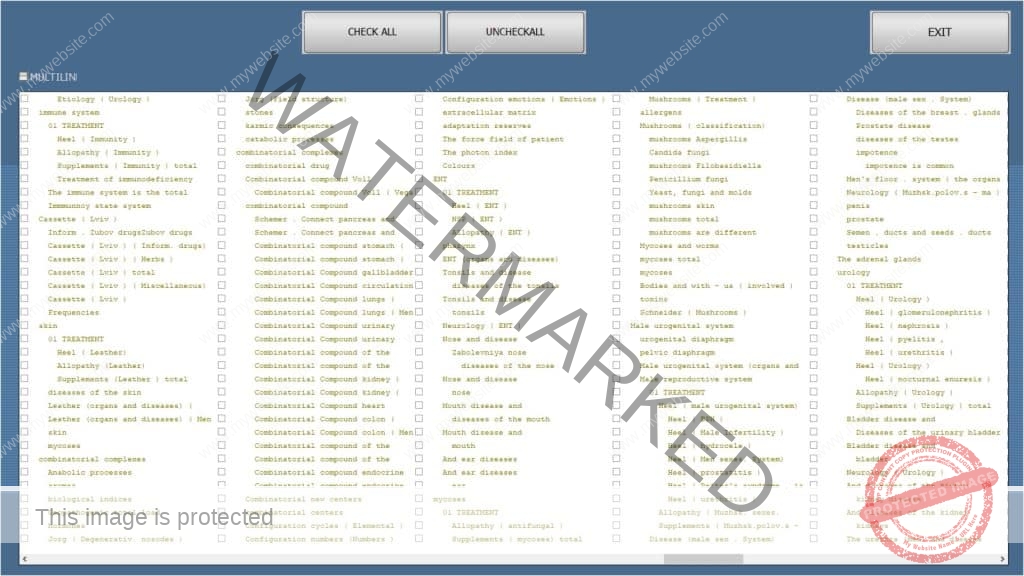

*A preview of the famous ISHA EXPERT SPECIALISTS PACKAGES : THE ISHA VIRUS PRO, THE ISHA DNA PRO, THE ISHA AURA PRO

ISHA DNA Expert Pro, with over 450 pairs of DNA + RNA + Chomosones, to easy select in 1 minut. While others only have 35+ pairs and we provide 100’s of etalons of many healing modalities and A-brand remedies, while others have only 35+ perhaps 50

ISHA AURA Command Expert Pro Physio, with the special Physiotherapy etalon, with Universal Rehabilitation wich costs in Bulgaria alone approx 3500 $. And we provide 100’s for a very nice low, even only a part of this price. So much much more and pay less. Also for Genetic disorders, Traumas, Curses, and many many more ….. just watch the free videos on google and on the forum.